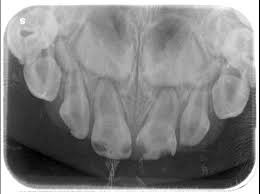

1. How old is the patient with the following X ray?